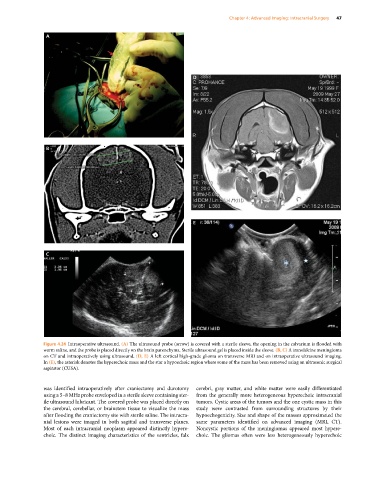

Figure 4.24 Intraoperative ultrasound. (A) The ultrasound probe (arrow) is covered with a sterile sleeve, the opening in the calvarium is flooded with

warm saline, and the probe is placed directly on the brain parenchyma. Sterile ultrasound gel is placed inside the sleeve. (B, C) A transfalcine meningioma

on CT and intraoperatively using ultrasound. (D, E) A left cortical high‐grade glioma on transverse MRI and on intraoperative ultrasound imaging.

In (E), the asterisk denotes the hyperechoic mass and the star a hypoechoic region where some of the mass has been removed using an ultrasonic surgical

aspirator (CUSA).